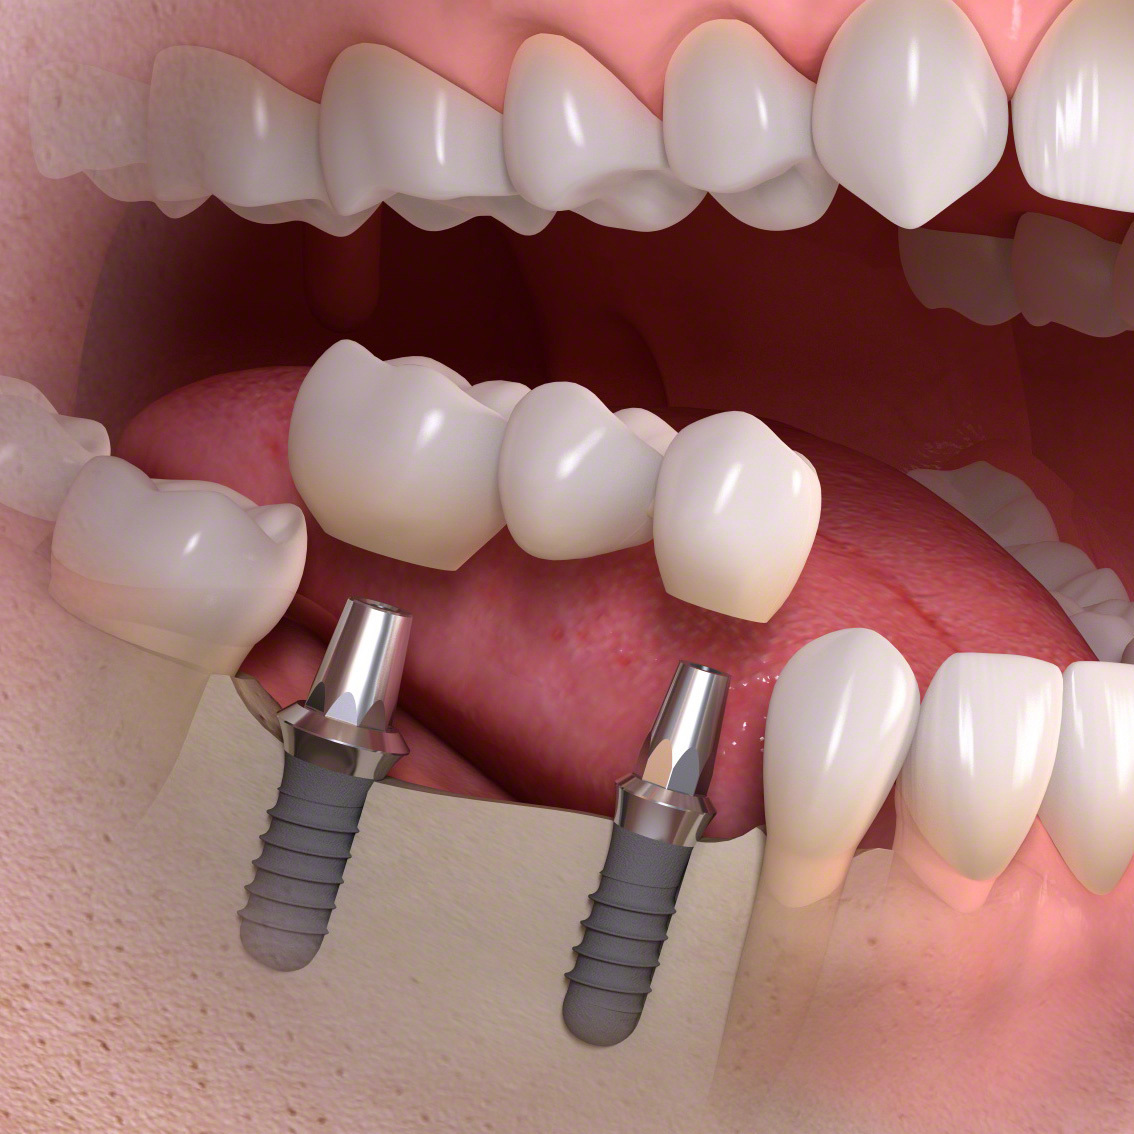

インプラントとは?

(通常のインプラント法)

歯科インプラントとは、歯を失った部分に人工歯根(主にチタン製)を外科的に埋め込み、その上にセラミックなどで作られた人工の歯を取り付けて、機能と見た目を回復する治療法です。

その後、一次手術としてインプラント体(フィクスチャー)を顎の骨に埋入し、数か月の治癒期間を経て骨としっかり結合させます。治癒後には二次手術を行い、歯肉からインプラントの上部構造を露出させます。なお、骨や歯肉の状態が良好な場合には、一次手術と二次手術を同時に行う「1回法」が選択されることもあります。

傷口が治った後に精密な型取りを行い、上部構造(人工歯)を製作・装着します。

インプラント(多数歯欠損ケース)

インプラントブリッジタイプ

・インプラントとインプラントでブリッジが可能です。

数本の歯を失った。

手術でインプラントを埋める。

インプラントに土台を接続します。

ブリッジタイプの被せ物を装着します。